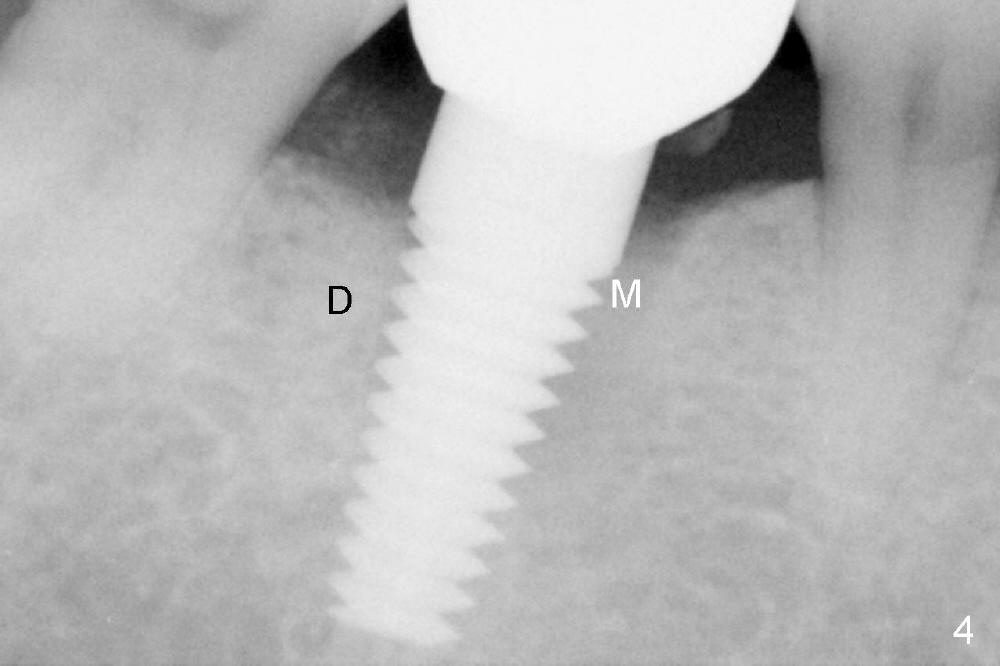

Thirteen months post bone graft via buccal approach, the patient has remained asymptomatic. There is no sign of infection buccally (Fig.1), but the lingual gingiva is erythematous (Fig.2 arrowheads) with deep pocket (Fig.3). Since the patient will be out of country for 7 months, exploration is going to be done immediately. Preop PA reveals mesial bone loss (Fig.4 M).

Upon flap reflection and granulation tissue curettage, the lingual threads are shown to be exposed with mesial bone resorption (Fig.5 <). The lingual defect is soaked with Clindamycin saturated gauzes (Fig.6 *), followed by copious irrigation, Emdogain application, bone graft and collagen dressing. The flap is sutured and covered by perio dressing.